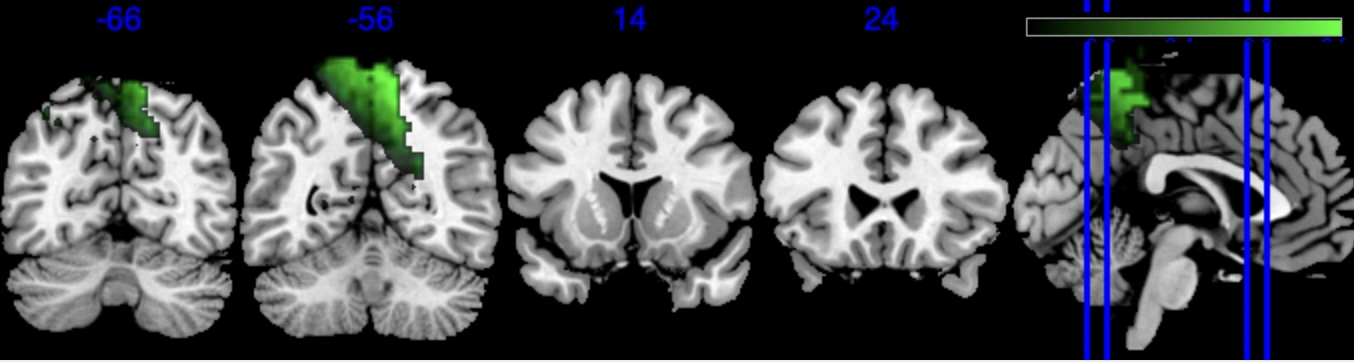

| Posterior inclusion probability (color range ) |

![]() |

| Positive posterior mean of the spatial mediation effects (color range ) |

| Negative posterior mean of the spatial mediation effects (color range ) |

We performed 100,000 iterations for the outcome model (1), discarding the first 50% as burn-in and thinning to retain 1,000 posterior samples. For the mediator model (2), we ran 40,000 iterations with a 30,000 burn-in, thinning every 10 iterations to obtain 1,000 posterior samples. Table 3 gives a summary of both the overall NIE and NDE and the top seven regions identified with the largest number of active voxels. The definition of NIE in each region is , where is the collection of all voxels in region . The rule for selecting the active voxels is based on cutting the posterior inclusion probability (PIP) at 50%, and the three regions with active voxels are reported in Table 3. Due to the very small effect sizes and low signal-to-noise ratio, we also include regions with voxels’ PIP greater than 10%. The posterior of NDE has a mean of 0.27 with the 95% credible interval . The posterior of NIE has a mean of 0.0885 with the 95% credible interval . The total effect of parental education level on general cognitive ability score is 0.36, with 95% credible interval (0.29,0.45). This suggests that parents with college degrees have a positive impact on children’s cognitive abilities, and about 25% of the effect is mediated through brain cognitive development. Figure 5 shows the estimated activation regions and the NIE in coronal view slides. Among the top identified activation regions, the most interesting is the left precuneus, which plays a key role in episodic memory, visuospatial processing, and self-consciousness (lou2004parietal; wallentin2006parallel). This region has been consistently implicated in cognitive processes related to memory retrieval and spatial awareness, which are crucial components of children’s cognitive development. In addition, other identified regions, such as the left inferior parietal region and the left postcentral gyrus, are associated with the interpretation of sensory information (radua2010neural; diguiseppi2023neuroanatomy). These regions are involved in integrating and processing sensory inputs, which are essential for tasks that require coordination between perception and cognition, such as working memory and executive function. These findings align with existing literature on the neural correlates of cognitive function, particularly in children. By identifying regions that have been consistently associated with cognitive processes, our results not only demonstrate the scientific validity of the BIMA approach but also provide meaningful insights into the brain areas that underlie cognitive abilities as captured by the ABCD study.